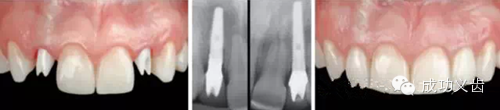

图7.众所周知,相连2颗下前牙的种植修复,考验医师的美学种植控制功力。

图8.相邻2颗下前牙,凸显美学种植控制功力,术后及模式图。在2015年4月3-5日的课程中,Dr.Gamborena将和大家分享他处理这类病例的技巧。绝对干货哦!

图9.再来一个高难度的病例。双侧下中切牙连种。

图10.再来一个高难度的病例。双侧下中切牙连种。牙龈乳头完美再生,毫无违和感。